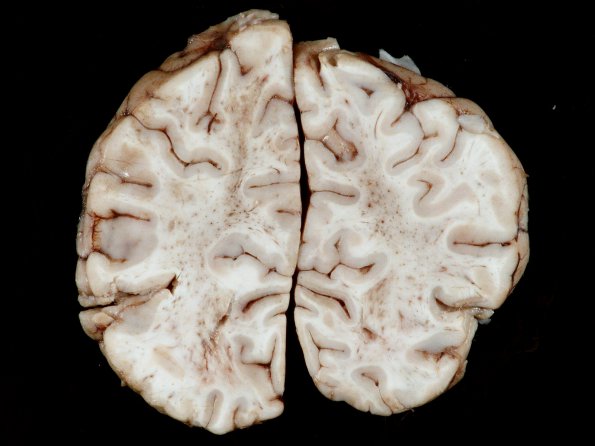

A coronal section of the cerebral hemispheres shows diffuse petechial hemorrhages and white matter discoloration.